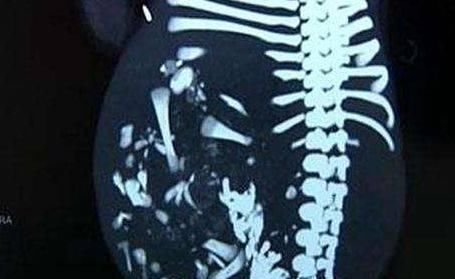

经过一系列的检查,医生告诉他们:萌萌的肚子里有一个寄生胎,也被称为胎中胎,这也就是为什么萌萌的肚子越来越大的原因。听完医生的话,家人难以接受。

所幸,手术很成功,萌萌肚子里的寄生胎被成功取出来了,萌萌也慢慢恢复了健康。

小编科普:谈到这种寄生胎,遗传学专家认为,有20%以上的妇女受孕后会出现怀有两个或两个以上的胎儿的现象,但等到胎儿发育到4~5个月时便只剩下一个了。妇产科医生也经常遇到这样的情况,不少产妇在拍X光检查或B超检查时,被告知是双胞胎,但分娩时却只有一个胎儿。出现这种现 象有两种原因,一种是胎儿着床不隐,除了一个胎儿扎根外,其余的被母体以某种方式吸收掉;另一种即「同室操戈」现象,一个强壮的胎儿为了争夺母体营养,将另一个或几个弱小的胎儿吸收掉或遏制其发育,或将其孪生兄弟的胚胎吸收包裹在自己的体内。这就是寄生胎儿,就可能是「同室操戈,相煎太急」的结果。